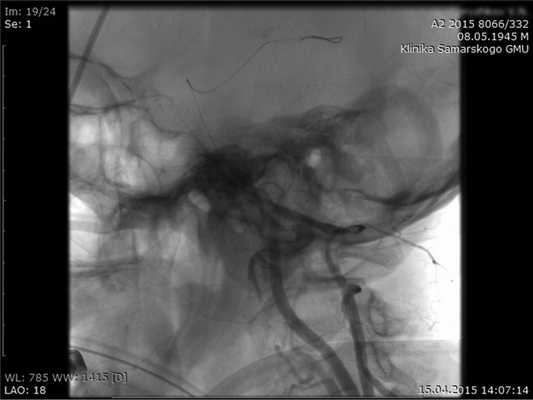

Вторым этапом в просвет общей СА ниже устья шунта на 3 см установили интродьюсер 5 Fr по направлению в голову. Выполнили ангиографию шунта. Провели через интродьюсер в шунт рентгенопозитивный проводник до дистальных отделов ОА и по нему выполнили ангиопластику и стентирование V4 сегмента левой ПА (рис. 4).

Рис. 4. Ангиопластика и стентирование V4 сегмента ПА.